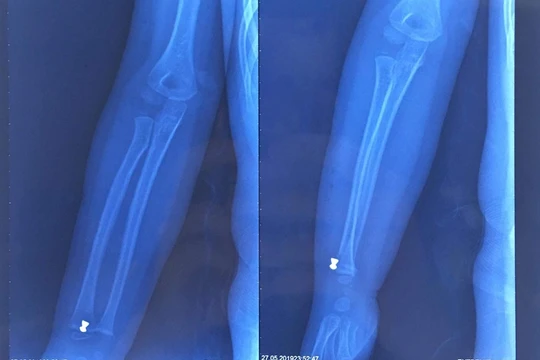

VietTimes -- Chiều 27/3, Bệnh viện đa khoa Xanh Pôn cho biết đang điều trị cho bệnh nhi Nguyễn T.H.Y (3 tuổi, ở Hà Nội) do bị chó pitbull cắn gãy xương đùi.